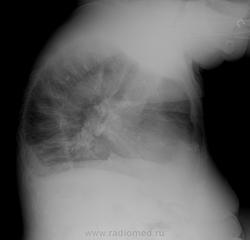

Плюсую к митральной конфигурации сердца. Думаю, что в легких не кальцинат, а суммация сосудов. На боковом такое предположение лучше подтверждается, и в "окрестностях" ещё есть сосуды.

Всё-таки кальцинат. Он на тень позвоночника проецируется. И в корнях кальцинаты таже есть.